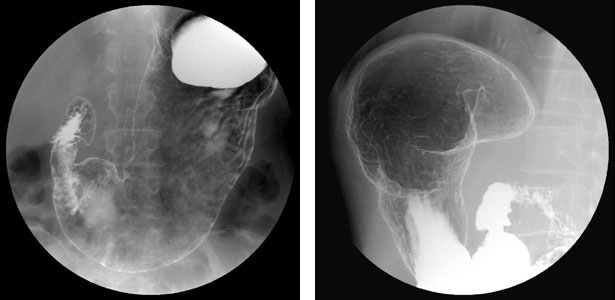

胃十二指腸造影(胃バリウム検査)

バリウムという造影剤を飲み、食道や胃、十二指腸などの内壁の様子を観察します。人間ドックや、食道・胃の精密検査などが対象となります。

バリウムを飲用する検査は、発泡剤も飲用し、胃を拡張し、胃のひだを伸展して検査する必要があります。

ゲップをすると拡張した胃が萎んでしまいます。

それを防ぐためにゲップを我慢していただきます。

万一ゲップしてしまっても、発泡剤を追加飲用して検査を続けることが可能です。

バリウムは粉末を水で溶いた造影剤です。

胃壁にバリウムを均一に付着させるために、検査台の上で体を回転していただきます。

検査が終了したら下剤をお渡ししています。バリウムは便秘を起こしやすいです。下剤を服用し水分を十分に摂っていただき早めに排泄されるよう心がけてください。

注)胃は、食べ物を腸へ送り出すためぜん動運動をしています。大きく収縮を繰り返すため、場合によっては検査に支障をきたします。そのため、検査内容によってはこの動きを抑制するための筋肉内注射を行うことがあります。